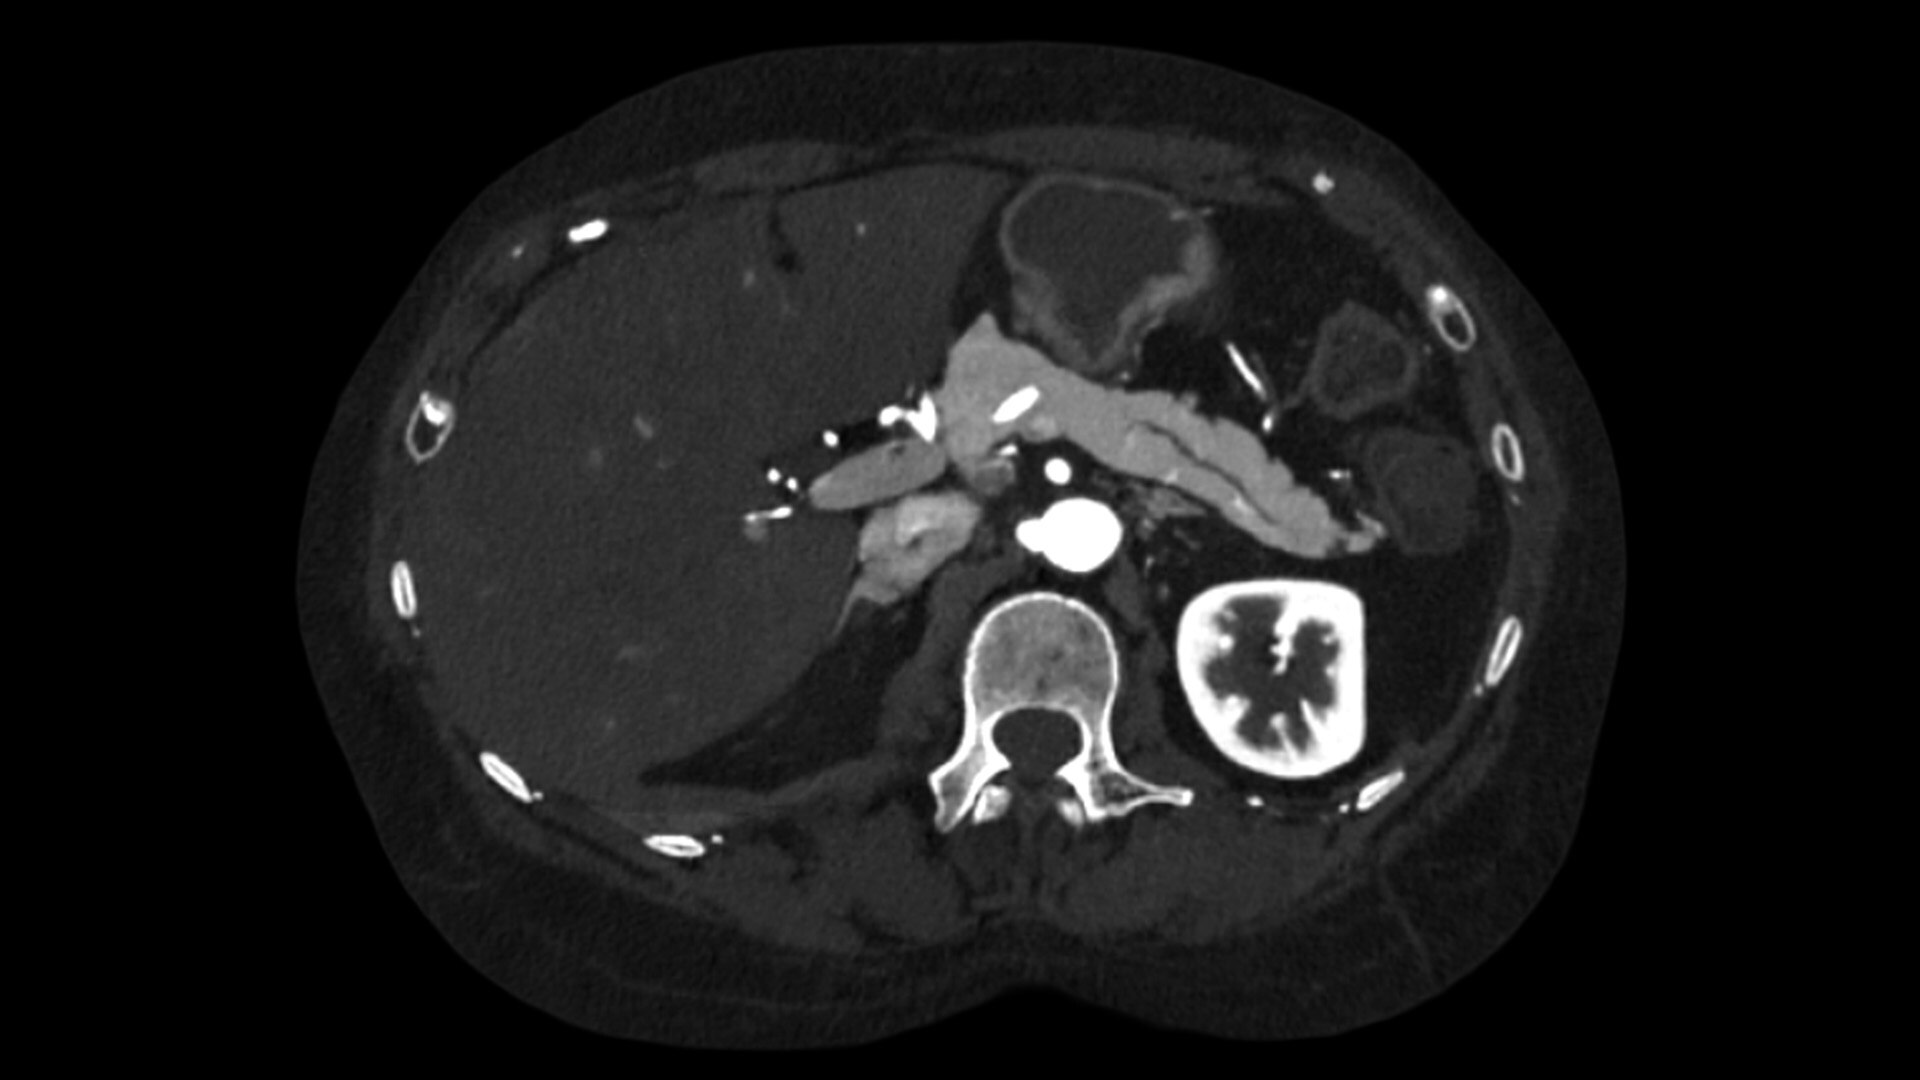

Photonova Spectra provides wide coverage in ultra-high definition imaging with exceptional acquisition speeds, designed to allow you to see your patient’s anatomy in exquisite detail.

With ultra-high spatial resolution scanning capability, Photonova Spectra is designed to help you see incredibly fine details, such as coronary plaque delineation, small microvascular vessels and even tiny structures of the inner ear.

Experience our industry-leading 8 cm detector coverage, combined with up to 0.23 sec rotation speed and ultra-high sampling rates featuring a 50 cm field of view (FOV) in all scan modes. This enables wide-coverage ultra-high definition imaging with reduced organ movement for exceptional image clarity.